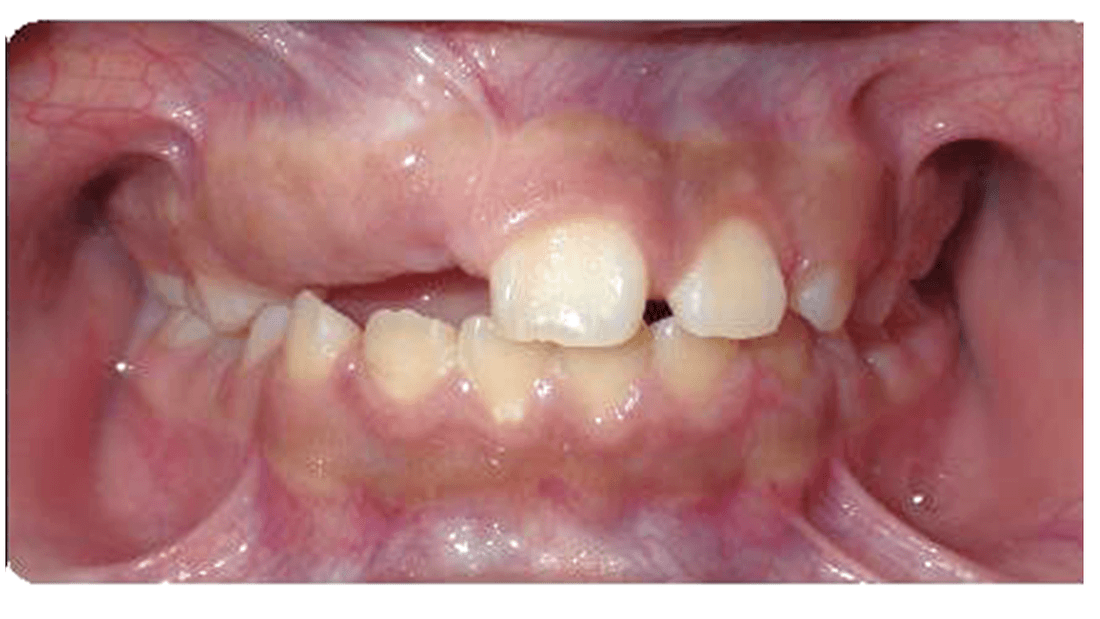

This patient presented with severe tooth misalignment, making it difficult for them to chew effectively. Our pediatric dentists corrected the situation with early orthodontic intervention using limited braces to address tooth alignment.

Early tooth correction sets the patient up for success for a second phase of tooth alignment with braces or clear aligners in the future.